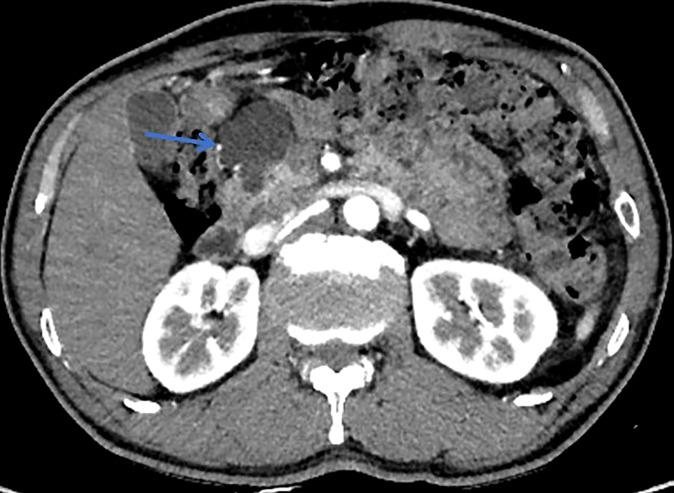

BACKGROUND/OBJECTIVES: There is no predictive model available to address early stage malignant intraductal papillary mucinous neoplasm (IPMN) including high grade dysplasia (HGD) and pT1a (invasive component≤0.5 cm). The aim of this study was to establish an objective and sufficient model to predict the degree of malignancy in patients with IPMN, which can be easily applied in daily practice and adopted for any type of lesion.

A retrospective cohort study of 309 patients who underwent surgical resection for IPMN was performed. Members of the cohort were randomly allocated to the training or testing set. A detection tree model and random forest model were used for a 3-class classification to distinguish low grade dysplasia (LGD), HGD/pT1a IPMN, and invasive intraductal papillary mucinous cancer (I-IPMC) beyond pT1a.

Of the 309 patients, 54 (17.4%) had early stage malignancy (19 HGD, 35 pT1a), 49 (15.9%) had I-IPMC beyond pT1a, and 206 (66.7%) had LGD IPMN. We proposed a 3-class classification model using a random forest algorithm, and the model had an accuracy of 99.5% with the training set, and displayed an accuracy of 96.0% with the testing set. We used SHAP for interpretation of the model and showed the top five factors (mural nodule size, main pancreatic duct diameter, CA19-9 levels, lesion edge and common bile duct dilation) were most likely to influence the 3-class classification results in terms of interpretation of the random forest model.

背景/目的:目前尚无预测模型可用于评估早期恶性导管内乳头状黏液性肿瘤(IPMN),包括高级别异型增生(HGD)和pT1a(浸润成分≤0.5 cm)。本研究的目的是建立一个客观且充分的模型,以预测IPMN患者的恶性程度,该模型可轻松应用于日常实践,并适用于任何类型的病变。

对309例行IPMN手术切除的患者进行回顾性队列研究。队列成员被随机分配到训练集或测试集。使用检测树模型和随机森林模型进行三类分类,以区分低级别异型增生(LGD)、HGD/pT1a IPMN和pT1a以上的浸润性导管内乳头状黏液癌(I-IPMC)。

在309例患者中,54例(17.4%)有早期恶性病变(19例HGD,35例pT1a),49例(15.9%)有pT1a以上的I-IPMC,206例(66.7%)有LGD IPMN。我们使用随机森林算法提出了一个三类分类模型,该模型在训练集上的准确率为99.5%,在测试集上的准确率为96.0%。我们使用SHAP对模型进行解释,并表明前五个因素(壁结节大小、主胰管直径、CA19-9水平、病变边缘和胆总管扩张)在随机森林模型的解释方面最有可能影响三类分类结果。